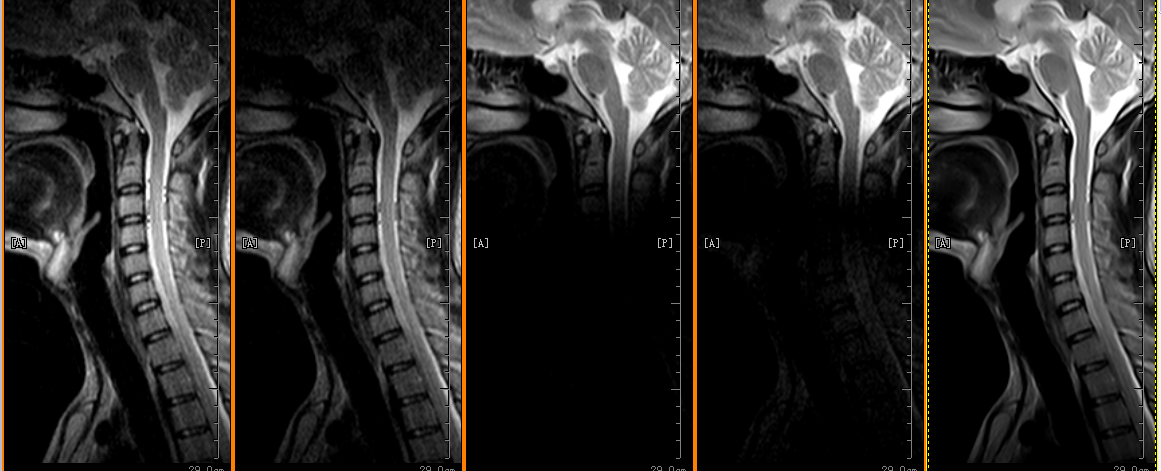

Thần kinh (não, tủy sống, dây thần kinh)

Cơ xương khớp (khớp, chi, cột sống)